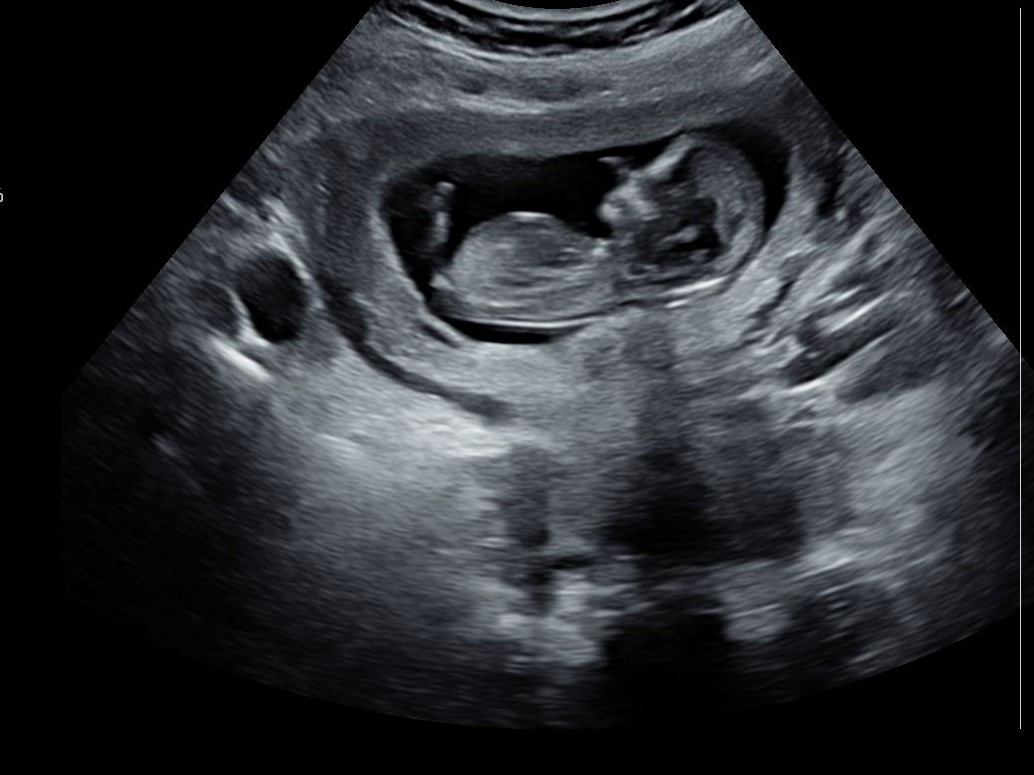

I have some other pictures maybe the nub is more visible on these

Was baby measuring 12 w exactly? Leaning girl based on the first and second pics in your last post.

Thx for your replies! Ultrasound was exactly at 12 weeks. I thought that was accurate for nub?

12 weeks is early and a flat nub could still rise. 13 weeks (or close to it) is ideal for a more accurate guess.

From the last pics you posted, I'd say those look more girl but like everyone has said, it's a tad early for nub guesses.